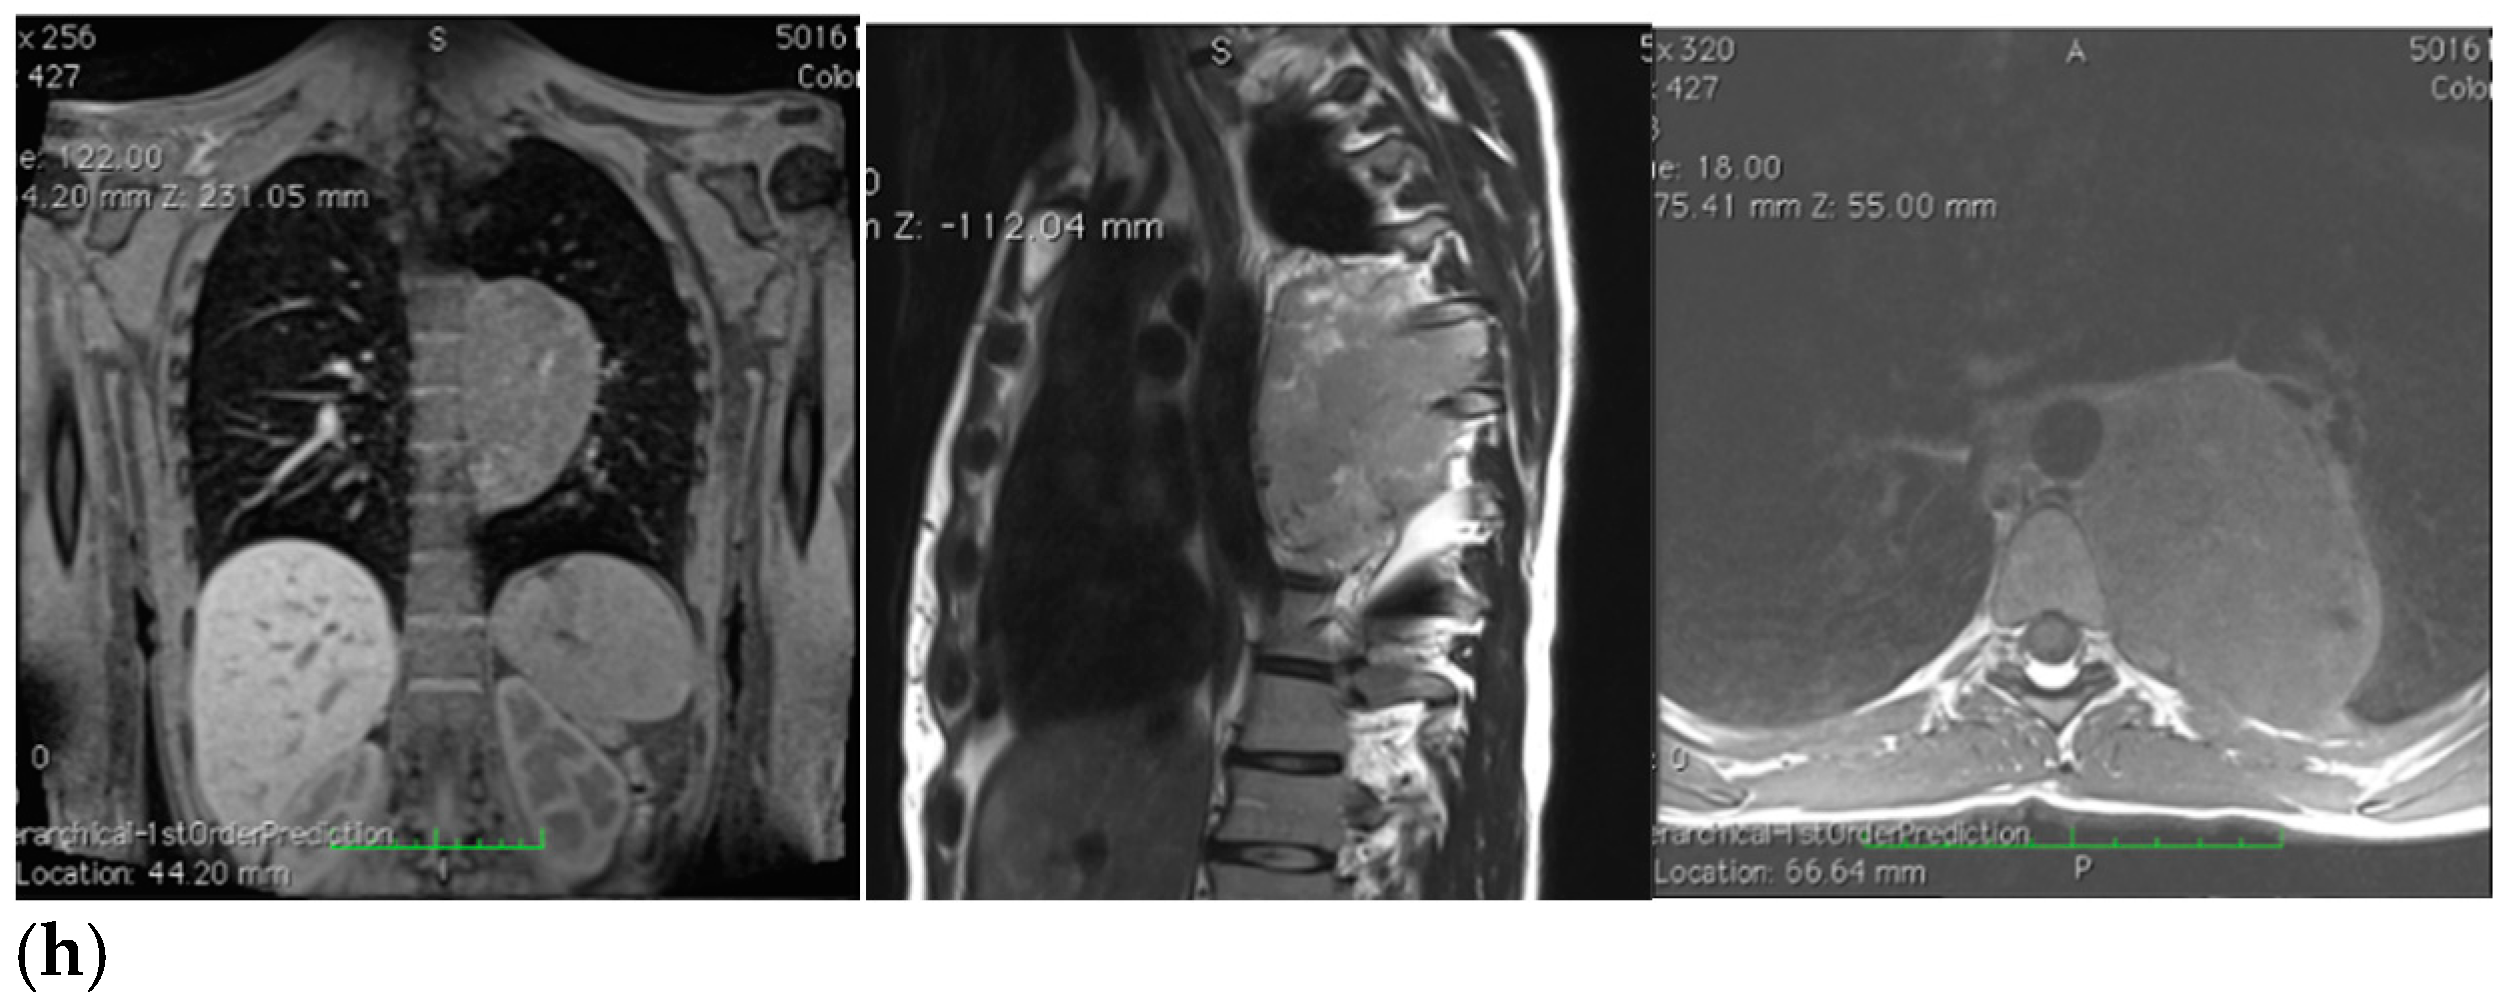

Figure 1.

(a–h) Imaging assessments for pre-surgical evaluation. (a) X-ray scans. (NOTE: Voluminous opacity in the posterior mediastinum on the left, with a major axis of about 12 cm). (b) Thorax CT scan with Iodixanol. (NOTE: Solid, oval-shaped tumour in the left posterior mediastinum, measuring 8 × 5.5 cm. Anteriorly, the mass pressed the left main bronchus from behind, while medially it displaced the thoracic aorta—sitting directly on the metamers T5 to T8, and compressing the hemiazygos vein. The mass also went through the intervertebral foramen, between T6 and T7, and partially through the VI and VII intercostal spaces; laterally, it caused dystelectasis of the lung parenchyma. The NB had an irregular density, with innumerable small foci of calcification, and areas of slightly blurred impregnation of the contrast medium). (c) Tracheobronchoscopy. (NOTE: Left lower lobe bronchus with a luminal narrowing, resembling an extrinsic compression. In detail: left lower lobe bronchus, left main bronchus, trachea and carina). (d) Thorax MRI with Gadoteridol. (NOTE: Presence of a mass with maximum dimensions of approximately 7.5 × 5.5 cm axially and 10 cm of craniocaudal extension, limited by a plane passing from upper T6 to lower T9. Extension up to the ipsilateral lung, which caused a moderate compression and a slight compressive effect, also on the left sections of the heart (in particular the atrium). Slight anterior displacement of the ipsilateral pulmonary hilum structures; the neoplasm also came into contact with the aorta. The tumour went through the left T6–T7 intervertebral foramen—taking up space at the foraminal level, not at the level of the spinal canal—and it also extended up the corresponding intercostal space; it was compatible with a lesion originating from the nerve sheath arising from the T6–T7 foraminal region). (e) Total-Body PET/CT. (NOTE: Presence of an increased glucose metabolism lesion in the posterior mediastinal area, showing a necrotic portion and a metabolically more active portion, located in the medial side and infiltrating the posterior arch of the 6th left rib). (f) Thorax CT scan with Lopromide. (NOTE: Minor volumetric increase of the known space-occupying lesion, which maintained similar densitometric characteristics, clear limits, and maximum diameters equal to 8.5 × 6 cm on the transverse plane, with a maximum longitudinal extension of 11 cm. The solid component which went through the intercostal space between T6 and T7 was substantially unchanged. Absence of pleural or pericardial effusion). (g) Total-body scintigraphy with metaiodobenzylguanidine. (NOTE: The examination confirmed that the neoplasm was confined to the mediastinum only. The area of greater contrast medium enhancement corresponded to the left hemithorax, in particular, to the left posterior mediastinal region, from T6 to T9). (h) Thorax MRI with Gadoteridol. (NOTE: Slight increase in size of the known space-occupying lesion in the posterior mediastinum (85 × 60 × 103 mm vs. 80 × 55 × 100 mm). At T6–T7 level, the mass occupied some left foraminal canal space. Next to the known lesion, pleural effusion thin layer (maximum thickness of 11 mm)).